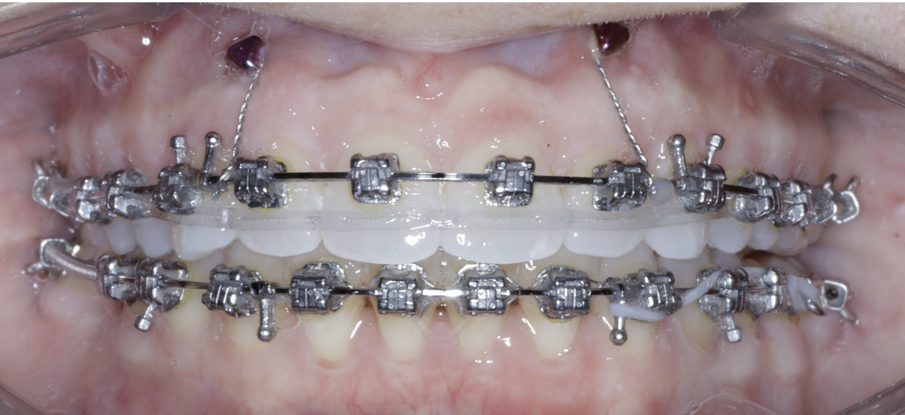

TADs are placed at the second visit with a 14 × 25 mm copper (Cu) and nickel–titanium (NiTi) wire and are tied from the anchor to the wire with an elastic thread (surgical thread; Fig. 6). Once the patient has progressed to larger Cu–NiTi wires and stainless steel, the TADs are tied to the wire using a power chain looped to the wire, or NiTi closing springs, depending on the thickness of the tissue (Figs. 7 & 8).